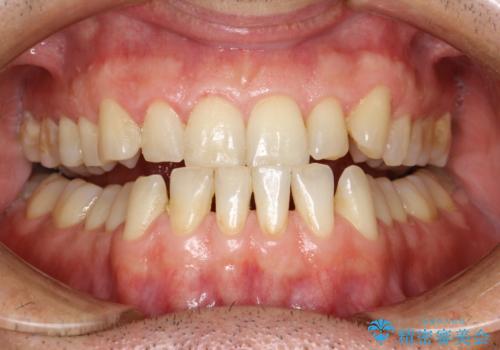

歯磨き中に血が出る PMTCで歯石除去

- 毎日の歯磨きの際に出血する。歯科でにクリーニンングをしばらくしていないとのことでした。PMTC60分コースを行いました。

歯磨きの際の出血は、歯肉炎や歯周病の症状とも言えます。歯周ポケットに歯周病菌が棲みつき、歯周病菌の出す毒素が歯茎に炎症を起こします。炎症が拡大し、歯周組織が破壊されたまま放置すると、最悪の場合、歯を支えている骨が溶かされ、歯がぐらぐらしてきます。